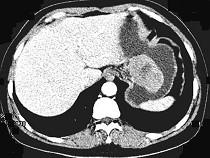

女,51岁,上腹部隐痛不适,CT检查如图,可能的诊断是 ( )A.胃癌B.胃息肉C.胃腺瘤D.胃溃疡E.胃间质瘤

问题 女,51岁,上腹部隐痛不适,CT检查如图,可能的诊断是 ( )

选项 A.胃癌 B.胃息肉 C.胃腺瘤 D.胃溃疡 E.胃间质瘤

答案 E